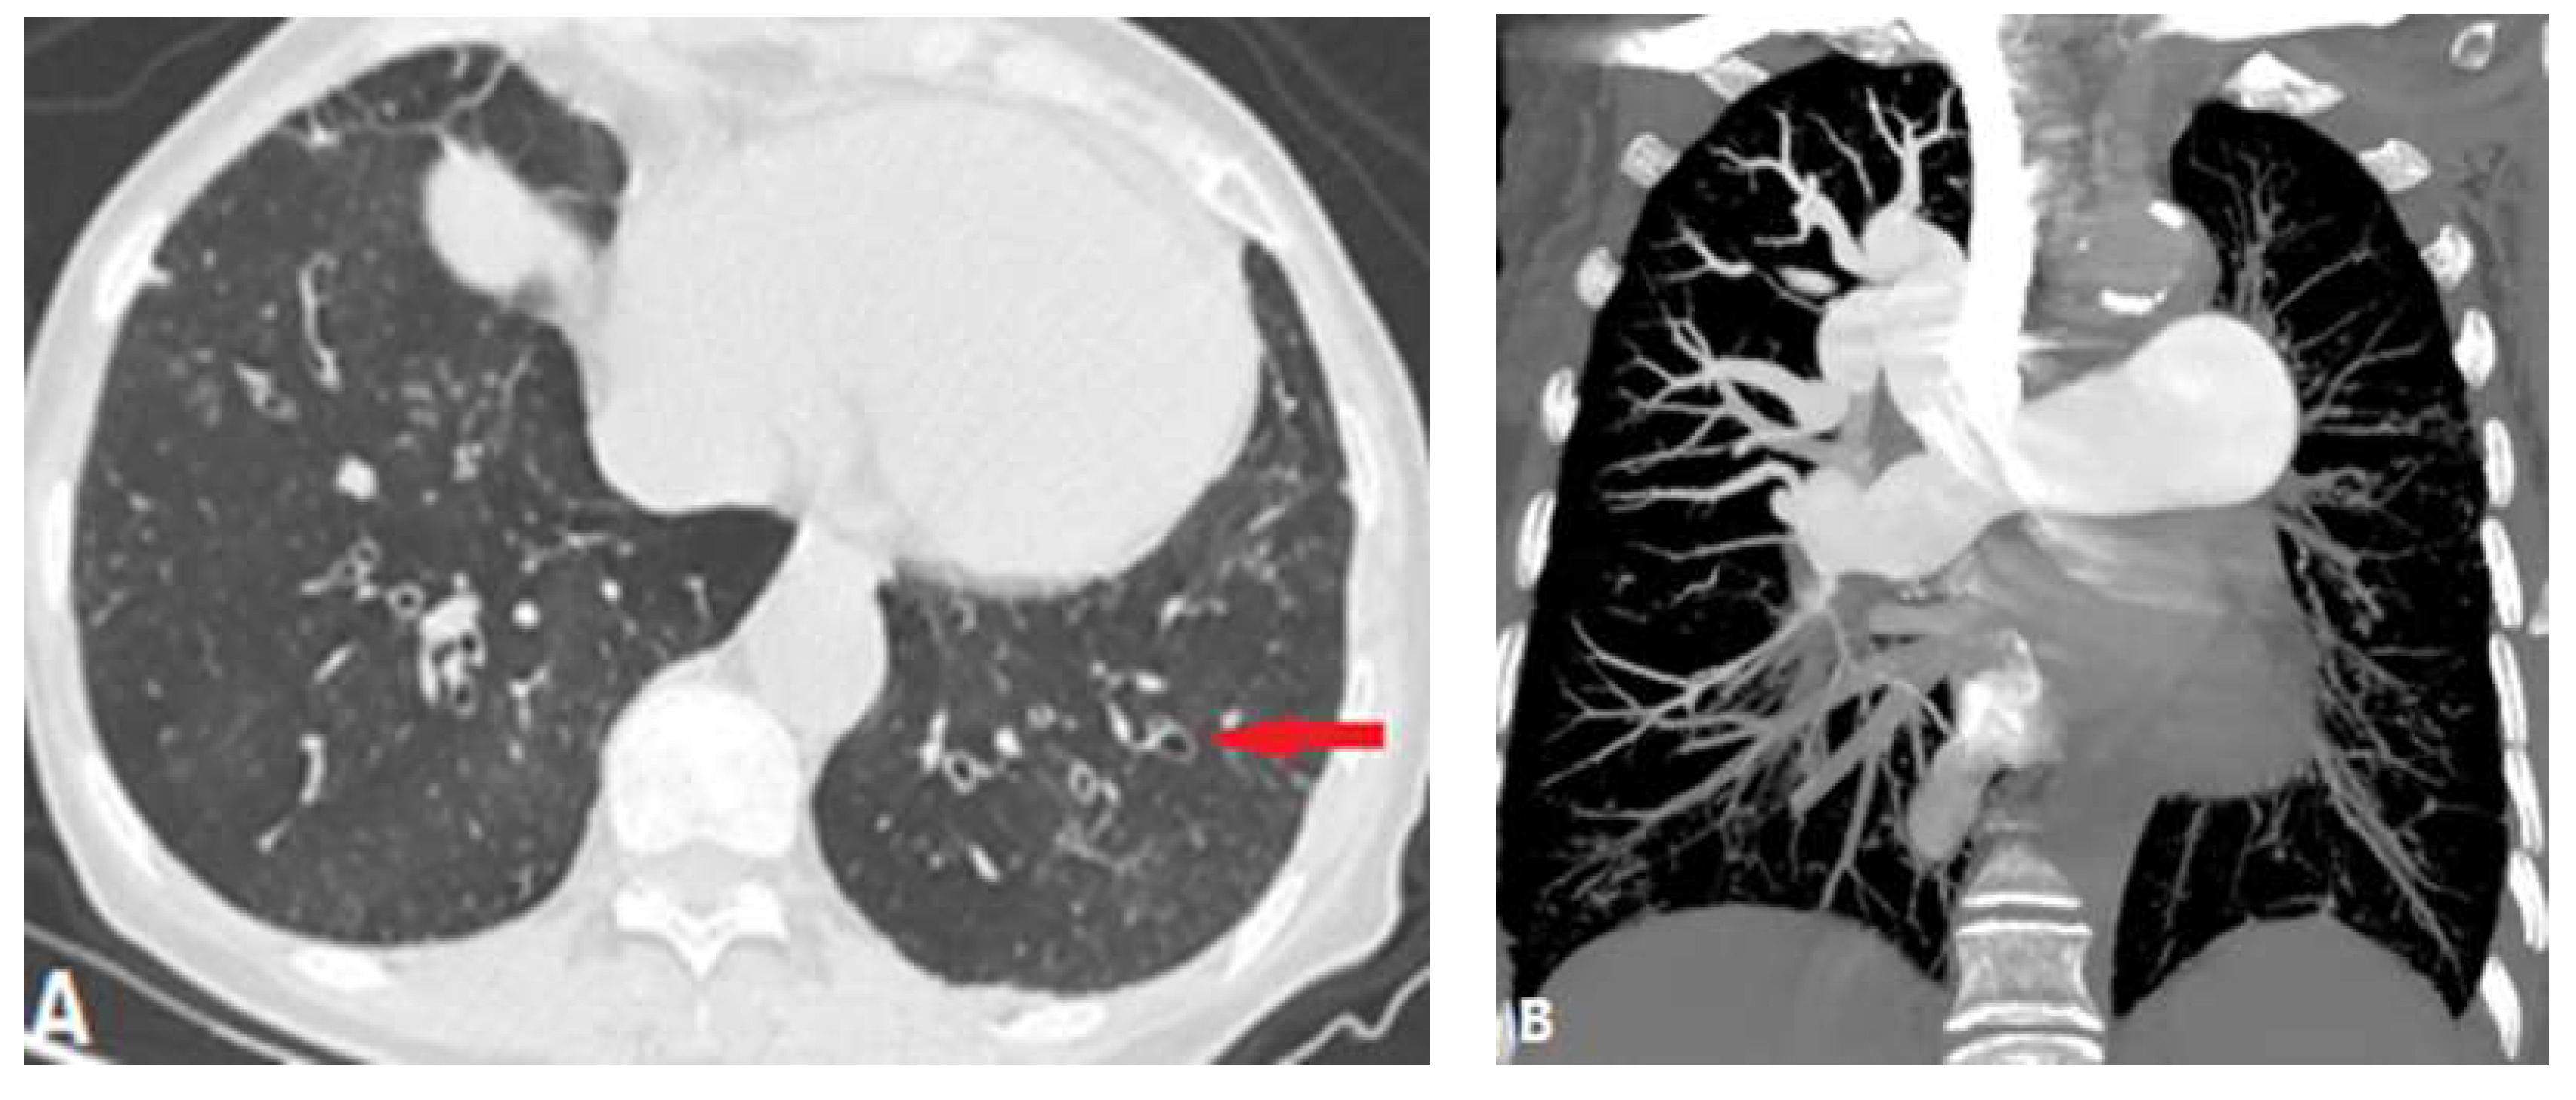

3.1.1. Pulmonary Thromboembolism (PTE)

3.1.2. In Situ Pulmonary Artery Thrombosis (PAT)